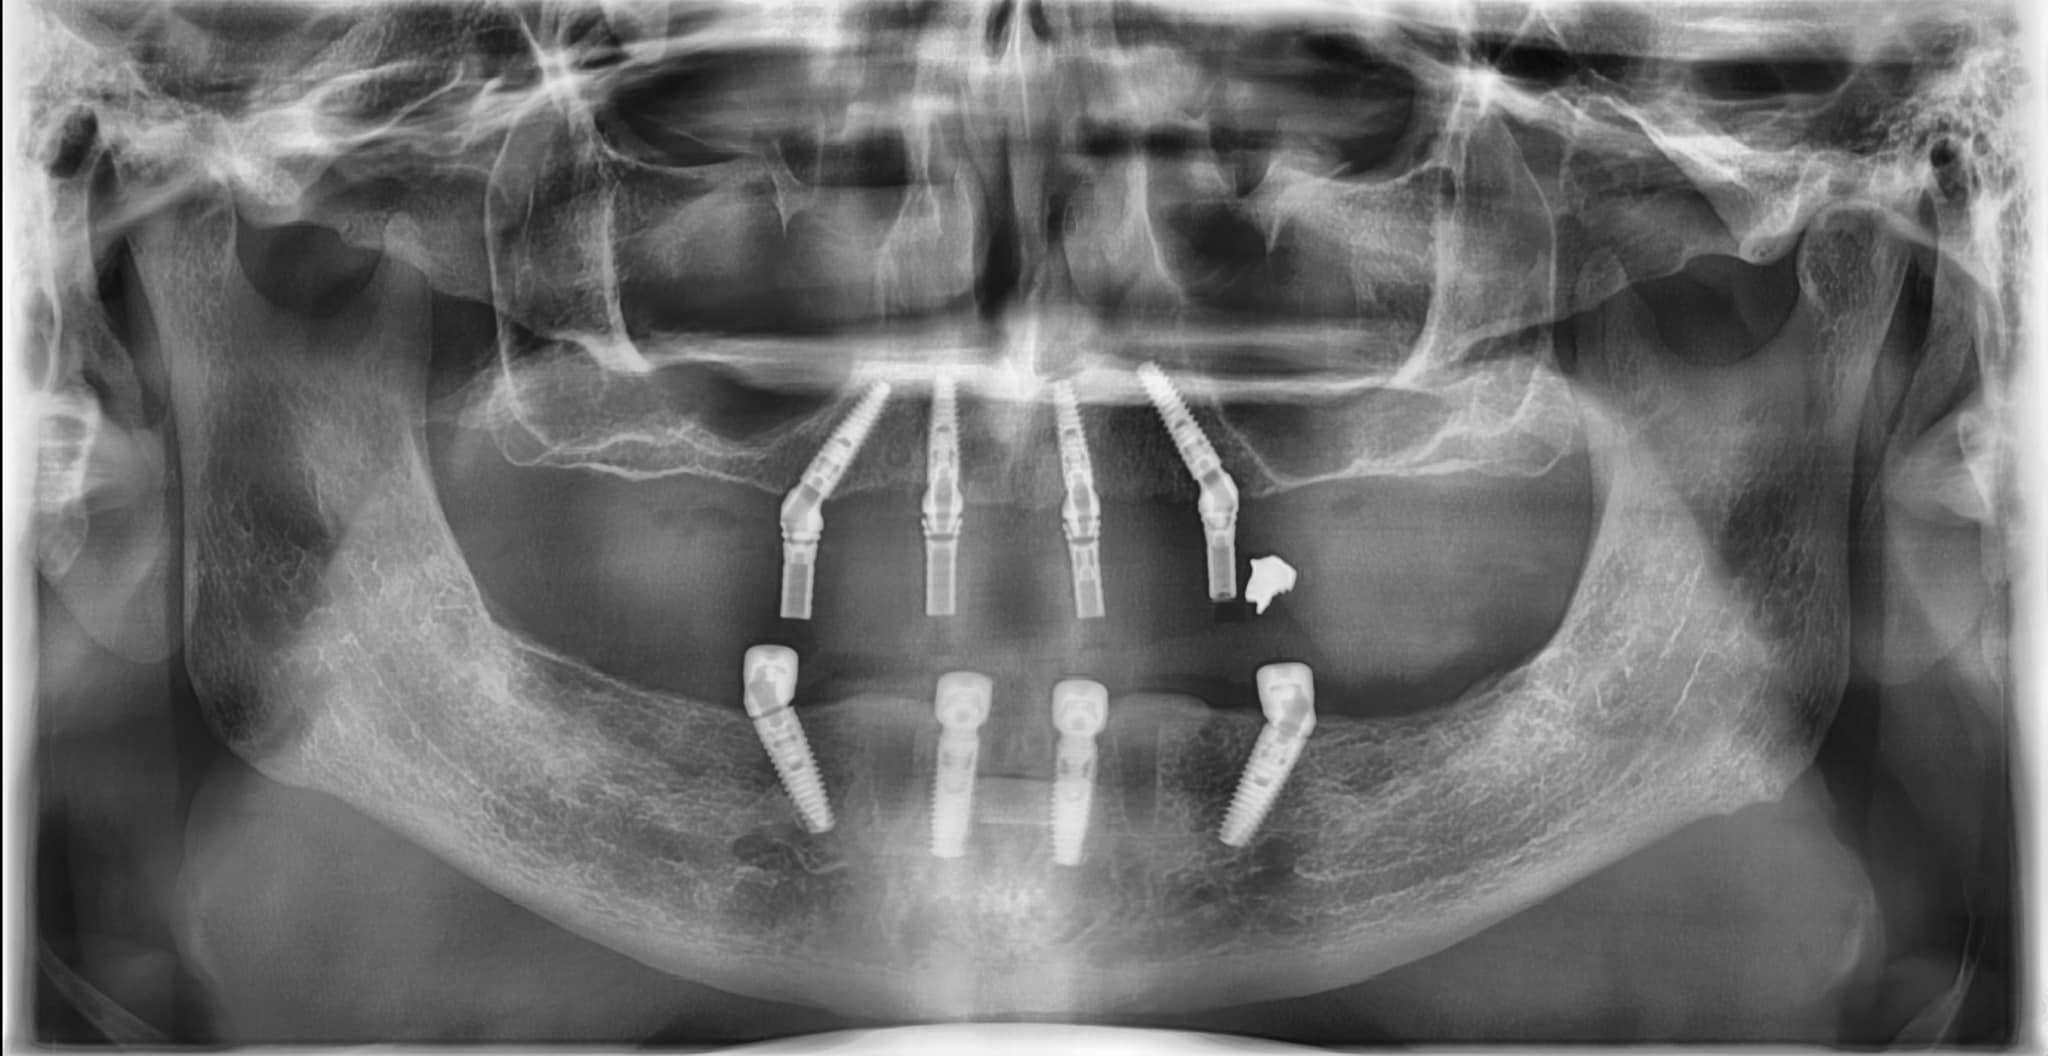

Phương pháp All on 4 chỉ sử dụng 4 trụ để nâng đỡ toàn hàm răng

Nếu như trước đây, việc trồng răng toàn hàm thường yêu cầu phải ghép xương bởi những trường hợp này thường mất răng lâu ngày dẫn đến hiện tượng tiêu xương, không đủ thể tích xương để nâng đỡ trụ Implant thì ngày này All on 4 đã khắc phục được vấn đề trên. Điều này không chỉ giúp bệnh nhân tiết kiệm được rất nhiều chi phí trồng răng implant mà còn giúp quá trình phục hồi được đẩy nhanh hơn. Chính bởi những ưu điểm rất lớn trong việc chỉ sử dụng bốn trụ implant cho một ca trồng răng toàn hàm nên nhiều người cho rằng mấu chốt của All on 4 là đặt bốn Implant đúng vị trí để đỡ được toàn hàm răng 1 cách vững chắc. Tuy nhiên, điều đó chưa đủ khi nói đến phương pháp Implant toàn hàm All on 4.

Trong buổi đào tạo All on 4 cho các Bác sĩ Bệnh viện Răng Hàm Mặt Sài Gòn - Đối tác chính thức của Malo Dental tại Việt Nam. Giáo sư Malo nhấn mạnh: Phương pháp trồng răng toàn hàm All on 4 là một tổ hợp từ việc chuẩn bị, tạo hình xương hàm ban đầu trước khi cắm implant, việc đặt các trụ implant ở vị trí phù hợp và quá trình phối hợp với Labo chuẩn bị răng giả phù hợp với hình dáng khuôn miệng. Ngoài việc xem xét về mặt thẩm mỹ, quy trình này còn đảm bảo sự thoải mái khi sử dụng và tính tự nhiên của răng giả. Điều này đòi hỏi việc lựa chọn vật liệu phù hợp, thiết kế răng phù hợp với khuôn mặt và sử dụng các công nghệ tiên tiến nhất trong ngành nha khoa.